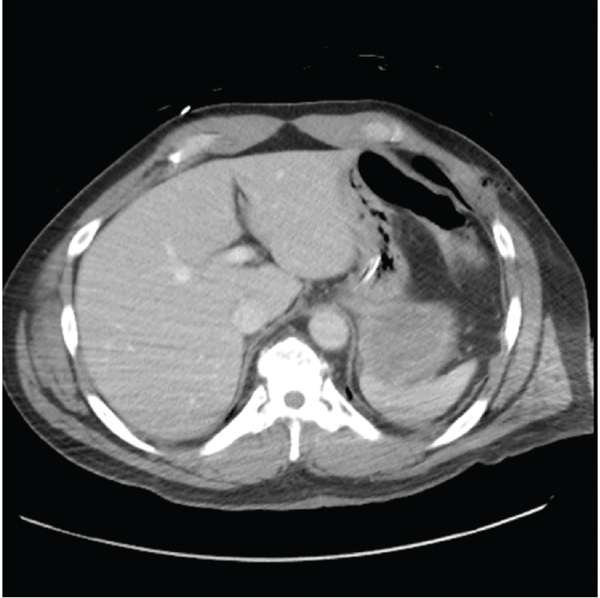

This patient is a 54-year-old homeless man with a history of schizophrenia who presented to the emergency department in November 2020 after being found down with a penetrating injury to the left anterior chest. On arrival, his GCS was 3, and he was being ventilated via bag valve mask by EMS. He was promptly intubated for airway protection. His vital signs were stable. On further exposure, he had an approximately 3 cm stab wound to his left anterior chest, medial to the nipple line, at approximately the level of the 7th rib. Otherwise, he was noted to have ecchymosis of the occiput and superficial lacerations to his right flank. Also concerning was a fixed and dilated left pupil. A pan CT scan revealed a left subdural hematoma with bilateral frontal hemorrhagic contusions and 5 mm of midline shift. Additionally, he was found to have a moderate left-sided pneumothorax and associated left anterior 7th rib fracture for which he underwent chest tube placement with resolution of his pneumothorax (Figure 2). A cerebral oxygenation monitor and drainage device was placed by neurosurgery revealing an elevated opening pressure of 31 mmHg. At this time, there was also concern for possible diaphragmatic injury given the location of his stab wound and imaging findings; however, in the setting of his elevated intracranial pressures, he was deemed unsafe for the OR and admitted to the neuro ICU for further monitoring.